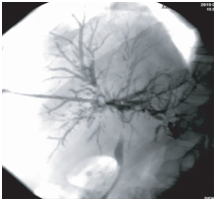

Figure 4 Cholangiography after BC removal. The first cholangiographic findings of the same patient after endoscopic therapy. Visualization of intrahepatic and extrahepatic bile ducts was improved, and patchy and tree-like negative shadows partially vanished.

BCs can prevent bile drainage, resulting in biliary obstruction and biliary tract infection. Percutaneous transhepatic cholangiography drainage is a common method for drainage of infected bile. After fistula extension, percutaneous transhepatic choledochoscopy can be implemented. We can observe the condition of the intrahepatic and extrahepatic bile ducts and remove multiple BCs with the help of choledochoscope, which is difficult by the conventional methods.19 In the process of removing BCs, we found that the BCs were shaped like the bile ducts, appearing as a hardened, dark material in the biliary ductal system with serious intrahepatic and extrahepatic bile duct injury. Some parts of the biliary mucosa showed patchy or strip defects, and mucosa ulcers were visible sometimes. After completely removing the BCs, the visualization of intrahepatic and extrahepatic bile ducts were improved, and patchy and bile duct mucosa were improved to varying degrees, showing reddish, smooth, rounded lumen and fresh bile secretion, and cholangiography displayed a very clear biliary tree (Figures 1–5).